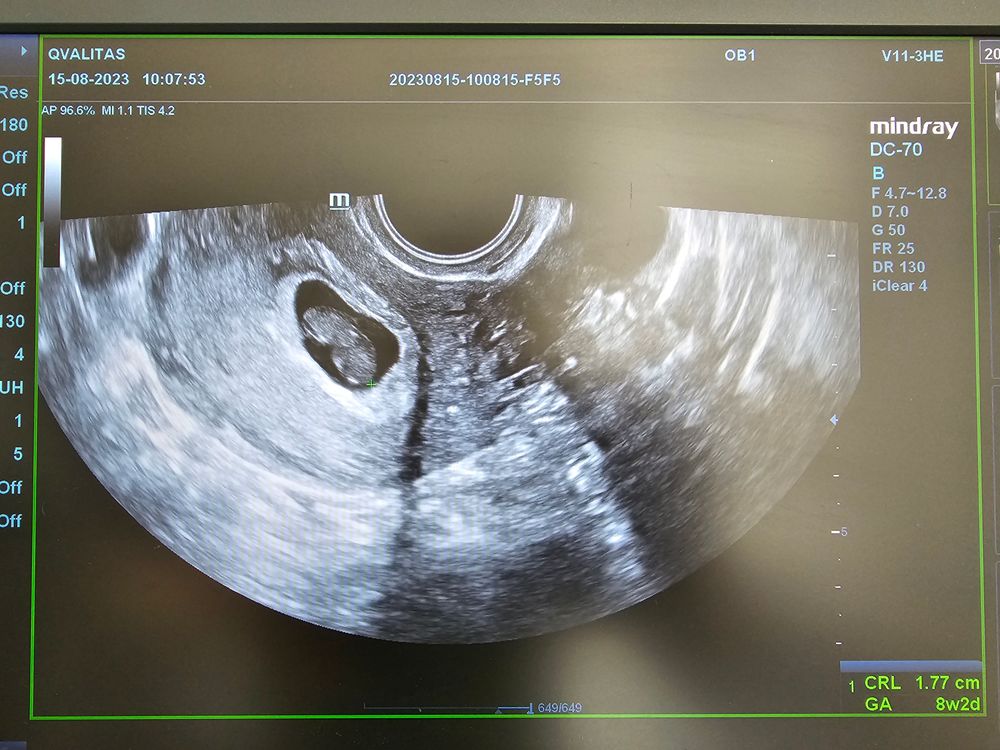

Сердце остановилось на сроке 8+2..